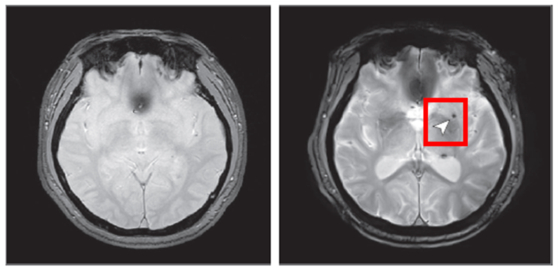

연구팀은 노화 심층조사사업 참여자 1441명을 8년 동안 추적해 수면무호흡증이 뇌 미세출혈 발생에 미치는 영향을 분석했다. 사진은 뇌 미세출혈이 발생하기 전(왼쪽)과 후 한 참여자의 뇌 영상 이미지. 사진 국립보건연구원 |

분석 결과, 중등도 이상의 폐쇄성 수면무호흡증을 가진 사람은 수면무호흡증이 없는 사람에 비해 뇌 미세출혈이 발생할 위험이 2.14배 증가하는 것으로 나타났다. 반면 경증 수면무호흡증에서는 위험 증가가 관찰되지 않았다. 이런 결과는 뇌혈관 질환 발생 위험과 관련된 특정 유전자(APOE ε4) 보유 여부와는 상관없는 것으로 나타났다. 수면무호흡증이 뇌 미세출혈 발생 위험을 높이는 독립적인 위험 요인이었다는 의미다.